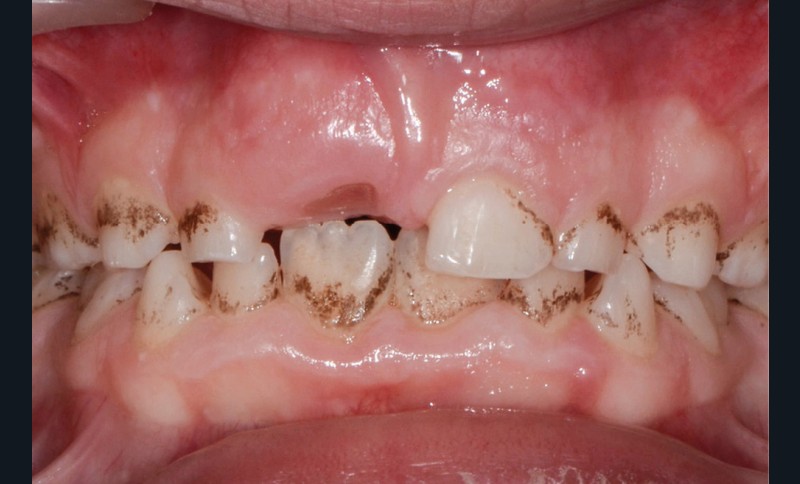

Elles sont causées par des agents colorants externes qui se déposent généralement sur la surface amélaire. Leurs origines sont diverses : alimentation (fig. 1b), tabac (fig. 1c), plaque bactérienne ou bactéries chromogènes (fig. 1d), ainsi que certains médicaments. La réalisation d’un aéropolissage en complément du détartrage initial est généralement suffisante pour éliminer efficacement ces colorations. Cependant, le patient doit être prévenu qu’en l’absence de modification de ses habitudes de vie, celles-ci reviendront [2, 4].